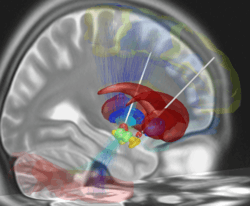

The deep brain stimulation system consists of three components: the implanted pulse generator (IPG), the lead, and the extension. The IPG is a battery-powered neurostimulator encased in a titanium housing, which sends electrical pulses to the brain to interfere with neural activity at the target site. The lead is a coiled wire insulated in polyurethane with four platinum-iridium electrodes and is placed in one or two different nuclei of the brain. The lead is connected to the IPG by the extension, an insulated wire that runs below the skin, from the head, down the side of the neck, behind the ear to the IPG, which is placed subcutaneously below the clavicle or, in some cases, the abdomen.[12] The IPG can be calibrated by a neurologist, nurse, or trained technician to optimize symptom suppression and control side-effects.[13]

DBS leads are placed in the brain according to the type of symptoms to be addressed. For non-Parkinsonian essential tremor, the lead is placed in the ventrointermediate nucleus (VIM) of the thalamus; for dystonia and symptoms associated with Parkinson's disease (rigidity, bradykinesia/akinesia, and tremor), the lead may be placed in either the globus pallidus internus or the subthalamic nucleus; for OCD and depression to the nucleus accumbens; for incessant pain to the posterior thalamic region or periaqueductal gray; for Parkinson plus patients to two nuclei simultaneously, subthalamic nucleus and tegmental nucleus of pons, with the use of two pulse generators; and for epilepsy treatment to the anterior thalamic nucleus.[14]

Deep brain stimulation represents an advance on previous treatments which involved pallidotomy (i.e., surgical ablation of the globus pallidus) or thalamotomy (i.e., surgical ablation of the thalamus).[52] Instead, a thin lead with multiple electrodes is implanted in the globus pallidus, nucleus ventralis intermedius thalami (Vim) or the subthalamic nucleus and electric pulses are used therapeutically. The lead from the implant is extended to the neurostimulator under the skin in the chest area.